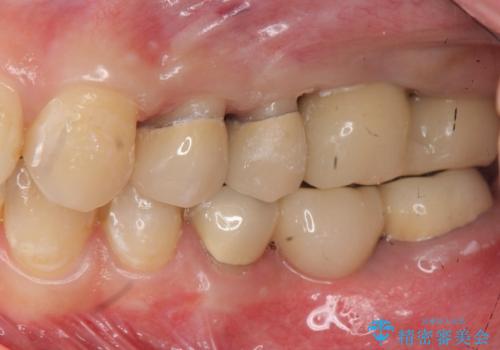

インプラント・セラミック・矯正治療を含む包括歯科診療

- 「地元の歯医者にずっと通っているが、どんどん歯が悪くなる。時間とお金がかかってもいいので徹底的に歯を治したい。」

、と総合的な歯科治療を希望されて来院されました。

虫歯や咬合関係・歯槽骨の吸収・根尖病変・歯の欠損・複合的な問題を一つずつ解決し、

安定した噛み合わせの構築・歯ブラシのしやすい環境の整備・歯内歯周の感染除去・造骨を伴うインプラント治療

を行い、長期的な予後を見込める口腔内環境を確立、整備して行きます。